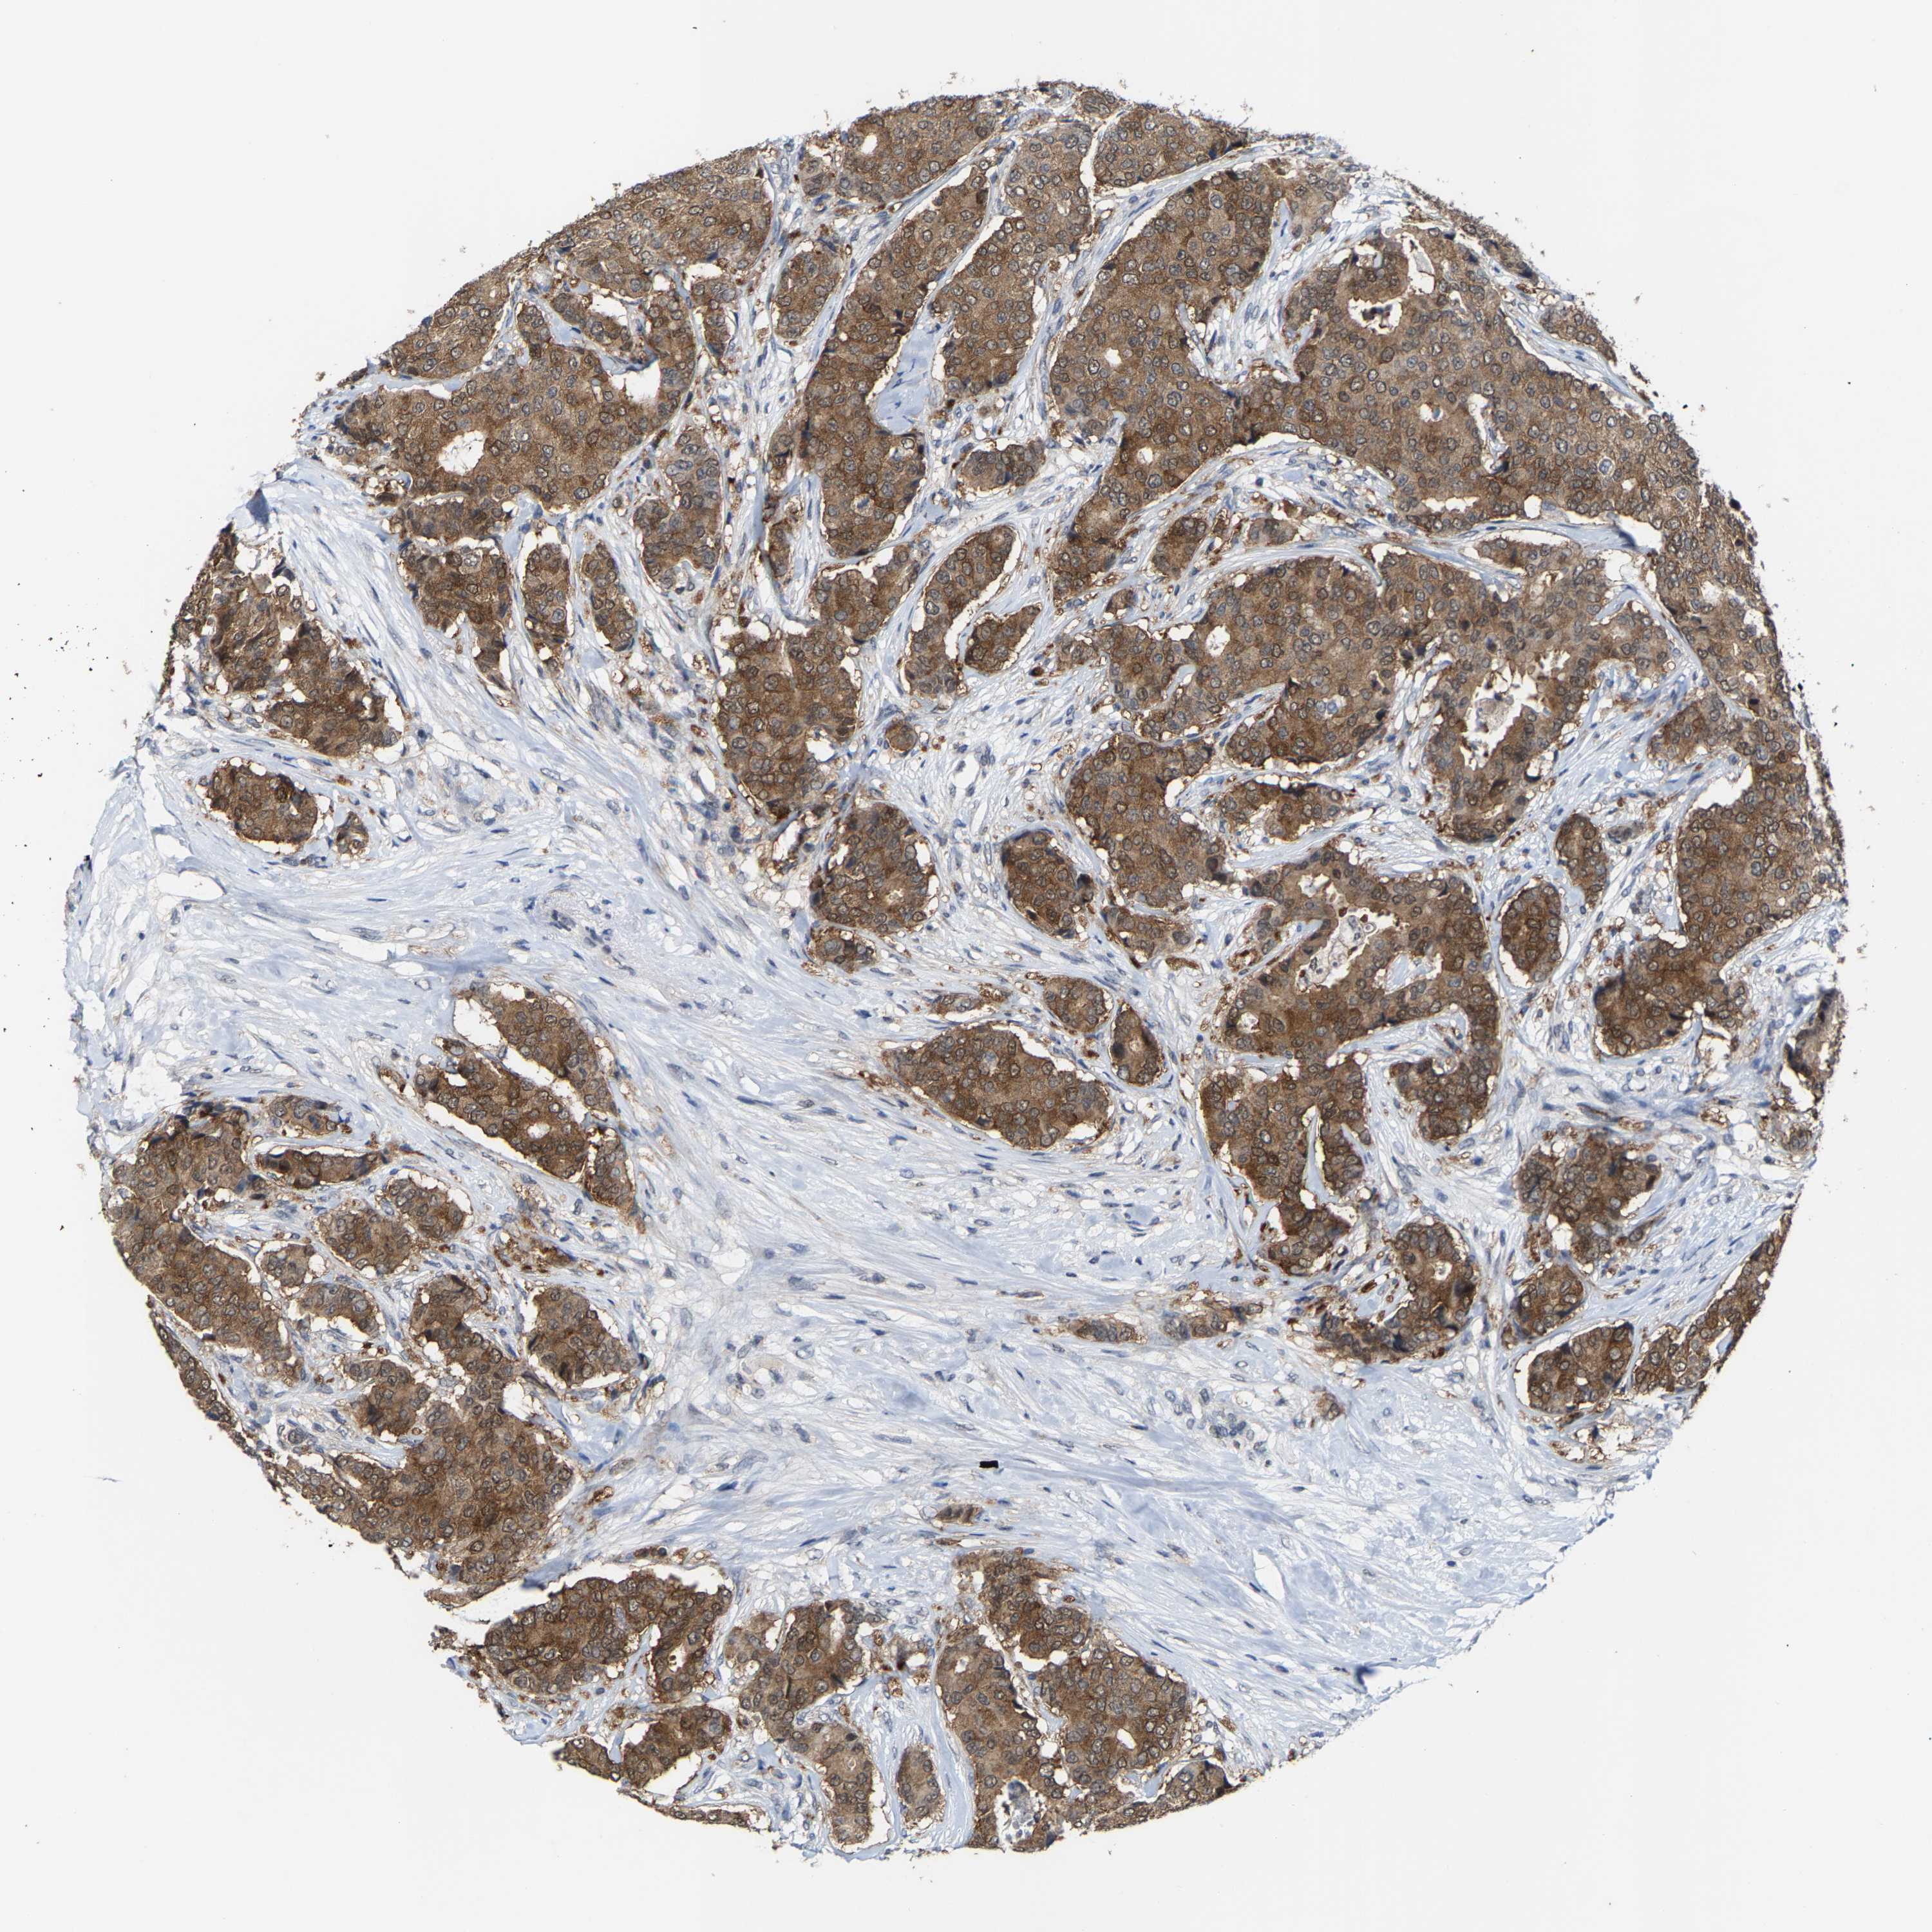

CANCER BREAST CANCER Show tissue menu

BRCA TCGA BRCA VALIDATION PROTEIN EXPRESSION